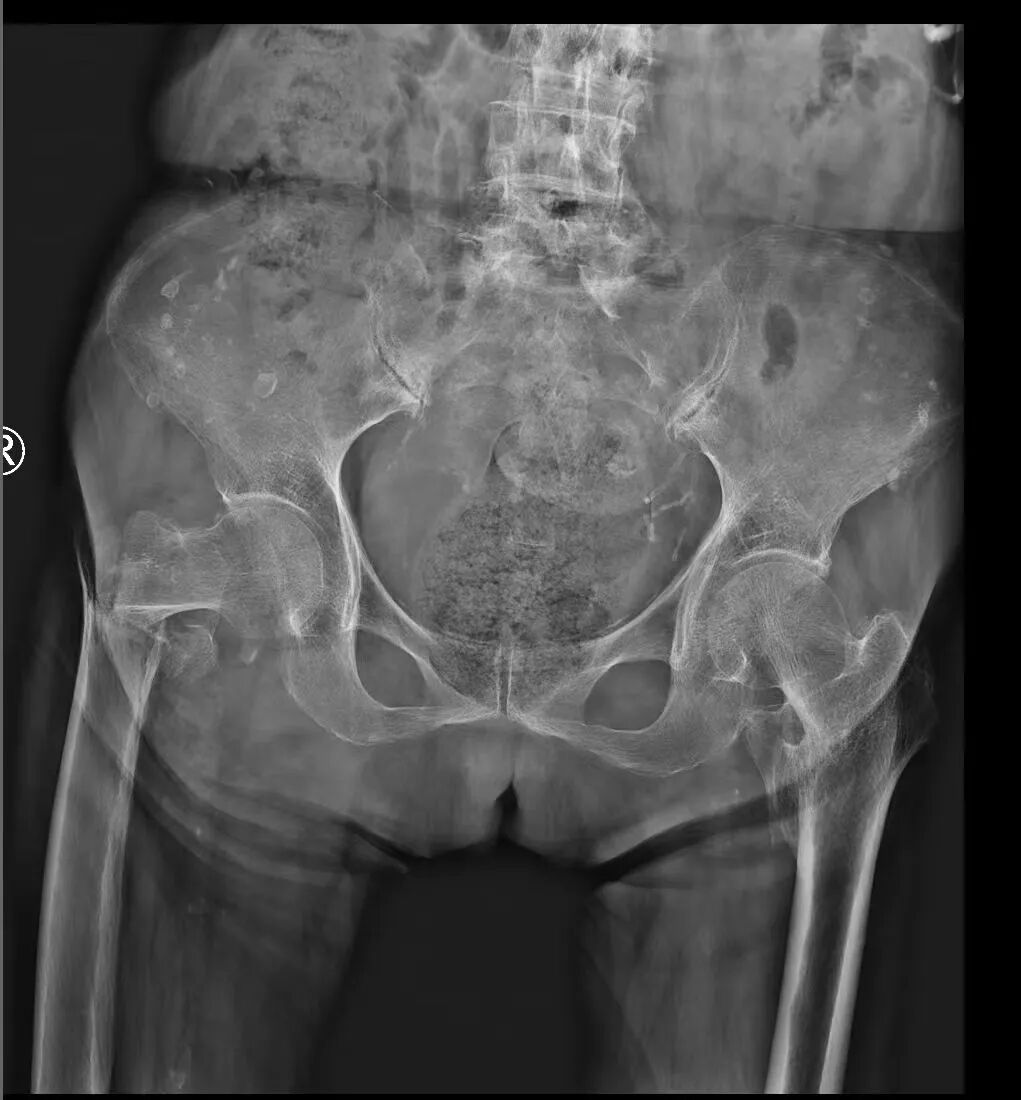

近日,一位101岁高龄的股骨粗隆间骨折患者,在西安市红会医院关节病院综合病区、心内科、麻醉科等多学科团队(MDT) 的精密协作与护航下,成功实施了直接前方入路(DAA)微创半髋关节置换术。此次手术突破了传统高龄骨折患者保守治疗的局限,不仅是一次技术上的成功,更是现代医院多学科协作模式应对超高龄、超高风险手术的典范之作,标志着医院在老年综合诊疗领域迈上新台阶。

股骨粗隆间骨折常见于高龄、骨质疏松的老年人,因其高致残率和死亡率,常被称为“人生最后一次骨折”。对于百岁老人而言,骨折后尽快恢复行走至关重要,而保守治疗需长期卧床,极易引发肺部感染、褥疮、血栓等致命并发症,内固定术后也难以实现尽早负重活动,因此,半髋关节置换术是最佳治疗方案。然而,为百岁老人实施手术,本身就是一场“刀尖上的舞蹈”。患者器官功能衰退,往往合并有多种基础疾病,对麻醉和手术的耐受性极差。任何一个环节的细微疏忽,都可能导致不可逆的后果。

在前期保障万无一失后,关节病院综合病区团队施展“绝技”。手术采用直接前方入路(DAA)微创技术,通过神经肌肉间隙入路,不损伤任何重要肌肉组织,切口小(7cm)、时间短(30分钟)、出血少(80ml),将手术本身对患者的生理打击降到了最低。患者术后无体位限制,术后即刻允许翻身、坐起,丝毫不用担心脱位风险。老人康复神速,术后第2天已能在医护人员辅助下下地站立行走活动,精神矍铄,笑容满面。